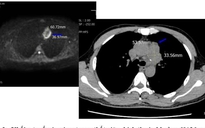

Bệnh nhân được phẫu thuật loại bỏ khối u ở 2 vị trí thanh quản và tuyến giáp

ẢNH: BVCC

Các bác sĩ đã phẫu thuật loại bỏ khối u ở cả 2 vị trí thanh quản và tuyến giáp. Ca mổ được thực hiện bằng dao siêu âm hiện đại, giúp hạn chế chảy máu và giúp người bệnh mau hồi phục.